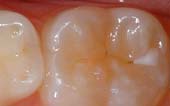

Seal Out Decay

A sealant is a protective coating that is applied to the chewing surfaces (grooves) of the back teeth (premolars and molars), where four out of five cavities in children are found. This sealant acts as a barrier to food, plaque and acid, thus protecting the decay-prone areas of the teeth.

Sealant-Before

Before Sealant Applied

Sealant-After

After Sealant Applied